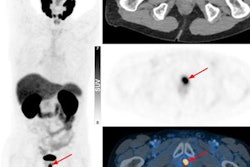

As with most imaging tests, PSMA-targeted PET imaging of prostate cancer patients has potential interpretive pitfalls and equivocal findings. PSMA-RADS 1.0 was introduced in 2018 by researchers at Johns Hopkins University School of Medicine in Baltimore, MD. The system is designed to provide guidance and structure in the interpretation and reading of PSMA-PET/CT scans using F-18 or gallium-68-labeled radiotracers.

The system is organized around a 5-point scale, with higher numbers indicating a greater probability of prostate cancer, Geyer explained. At the lower end of the scale, PSMA-RADS-1 and PSMA-RADS-2 lesions are either certainly or almost certainly benign, while PSMA-RADS-4 indicates a high likelihood that prostate cancer is present and PSMA-RADS-5 lesions almost certainly represent cancer in patients, he said. Primarily, lesions are classified based on how much radiotracer uptake is observed on the PET/CT scans.